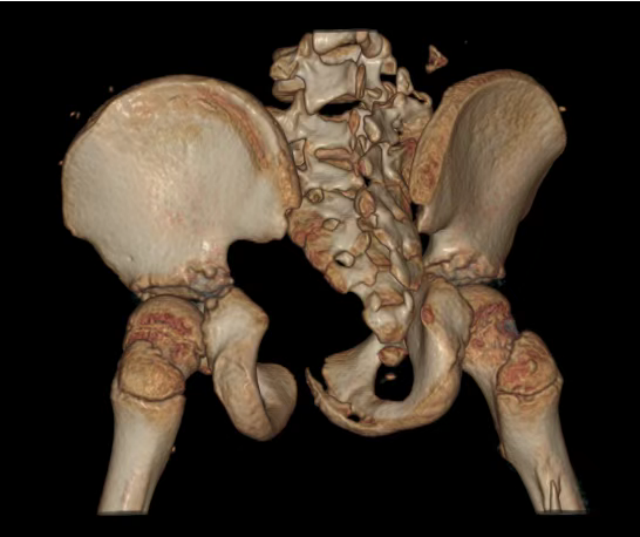

术前患儿影像,可见大面积血肿

术前患儿影像,可见盆骨骨折